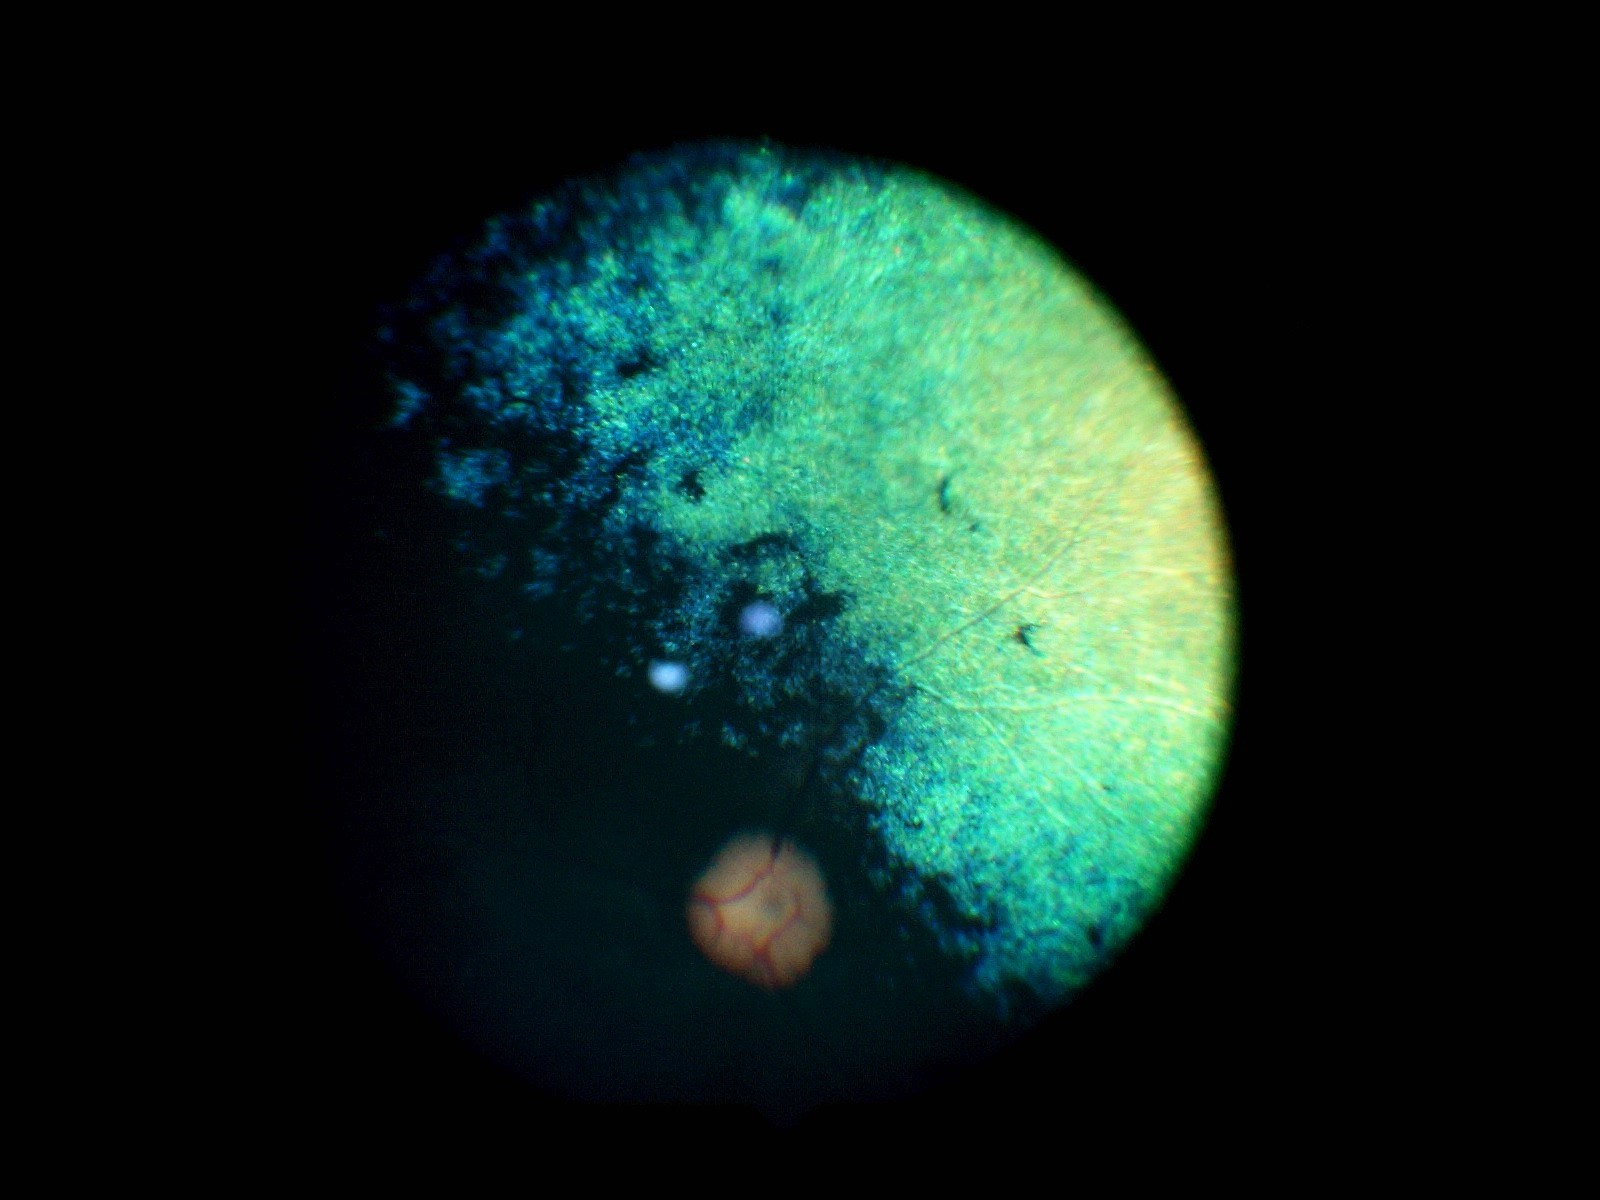

Bei der klassischen PRA beginnen die „Stäbchen“ die für das Nachtsehen zuständig zuerst zu degenerieren bzw. abzusterben. Dieser Vorgang ist nicht schmerzhaft. Im Anfangsstadium ist auffällig, dass sich die Tiere im Dämmerlicht oder im Dunkeln unsicher bewegen, ängstlich sind und unbekannte Objekte oder Personen verbellen. Teilweise stoßen die Tiere auch gegen ihnen unbekannte Dinge an oder weichen dem Besitzer nicht mehr von der Seite. Ein weiteres Zeichen ist der unvollständige Schluss der Pupillen bei einfallendem Licht und ein stärkeres “Leuchten” der Augen in der Dunkelheit als gewöhnlich, was ein Zeichen für eine dünner werdende Netzhaut ist. Dadurch kommt die unter der Netzhaut gelegene Schicht, das leuchtende Tapetum lucidum, verstärkt zum Vorschein. Diese Symptome verschlechtern sich dann in den darauffolgenden Monaten bis Jahren und führen zu einer spürbaren Sehverschlechterung auch im hellen Licht, da dann auch die „Zapfen“ beginnen zu degenerieren. Auch dieser Vorgang ist nicht schmerzhaft. Zwischen den ersten Symptomen und der vollständigen Erblindung vergehen in der Regel 3-6 Jahre.  Selten gibt es PRA Formen, bei welchen zuerst die Zapfen und im Anschluss daran die Stäbchen degenerieren. Dann tritt genau der umgekehrte Fall ein und die Tiere erblinden zuerst bei hellem Licht und anschließend auch bei Dunkelheit, dies sind Sonderformen und enden leider auch immer mit der vollständigen Erblindung des Tieres. Eine häufige Folgeerkrankung der PRA stellt der graue Star (Katarakt oder Eintrübung der Linse) dar. Als Folge des grauen Stars kann nach einigen Jahren der grüne Star (Erhöhung des Augeninnendrucks) auftreten. Der grüne Star gehört mit zu den schmerzhaftesten Erkrankungen des Auges und kann zum Verlust des gesamten Augapfels führen. Aus diesem Grunde sollten Tiere, die an der PRA erkranken, ca. einmal jährlich zu einer Kontrolluntersuchung der Augen vorgestellt werden, damit weitere Folgeschäden frühzeitig erkannt und dann behandelt werden können, um schmerzhafte Zustände zu vermeiden.

Ein auf Augenerkrankungen spezialisierter Tierarzt (Veterinär-Ophthalmologe) kann die Diagnose PRA anhand der typischen Symptome und der Befunde stellen, sobald die Erkrankung klinisch ausgebrochen ist, d.h. sobald auch nur geringe Anzeichen einer Sehschwäche auffällig werden. In Einzelfällen, in denen z.B. der graue Star die Sicht auf die Netzhaut verhindert, kann die Diagnose auch mit Hilfe eines Elektroretinogrammes (ERG) gestellt werden. Das ERG ist eine Untersuchung der Netzhautfunktionen, die mit einem EKG (Elektrokardiogramm) des Herzens verglichen werden kann.